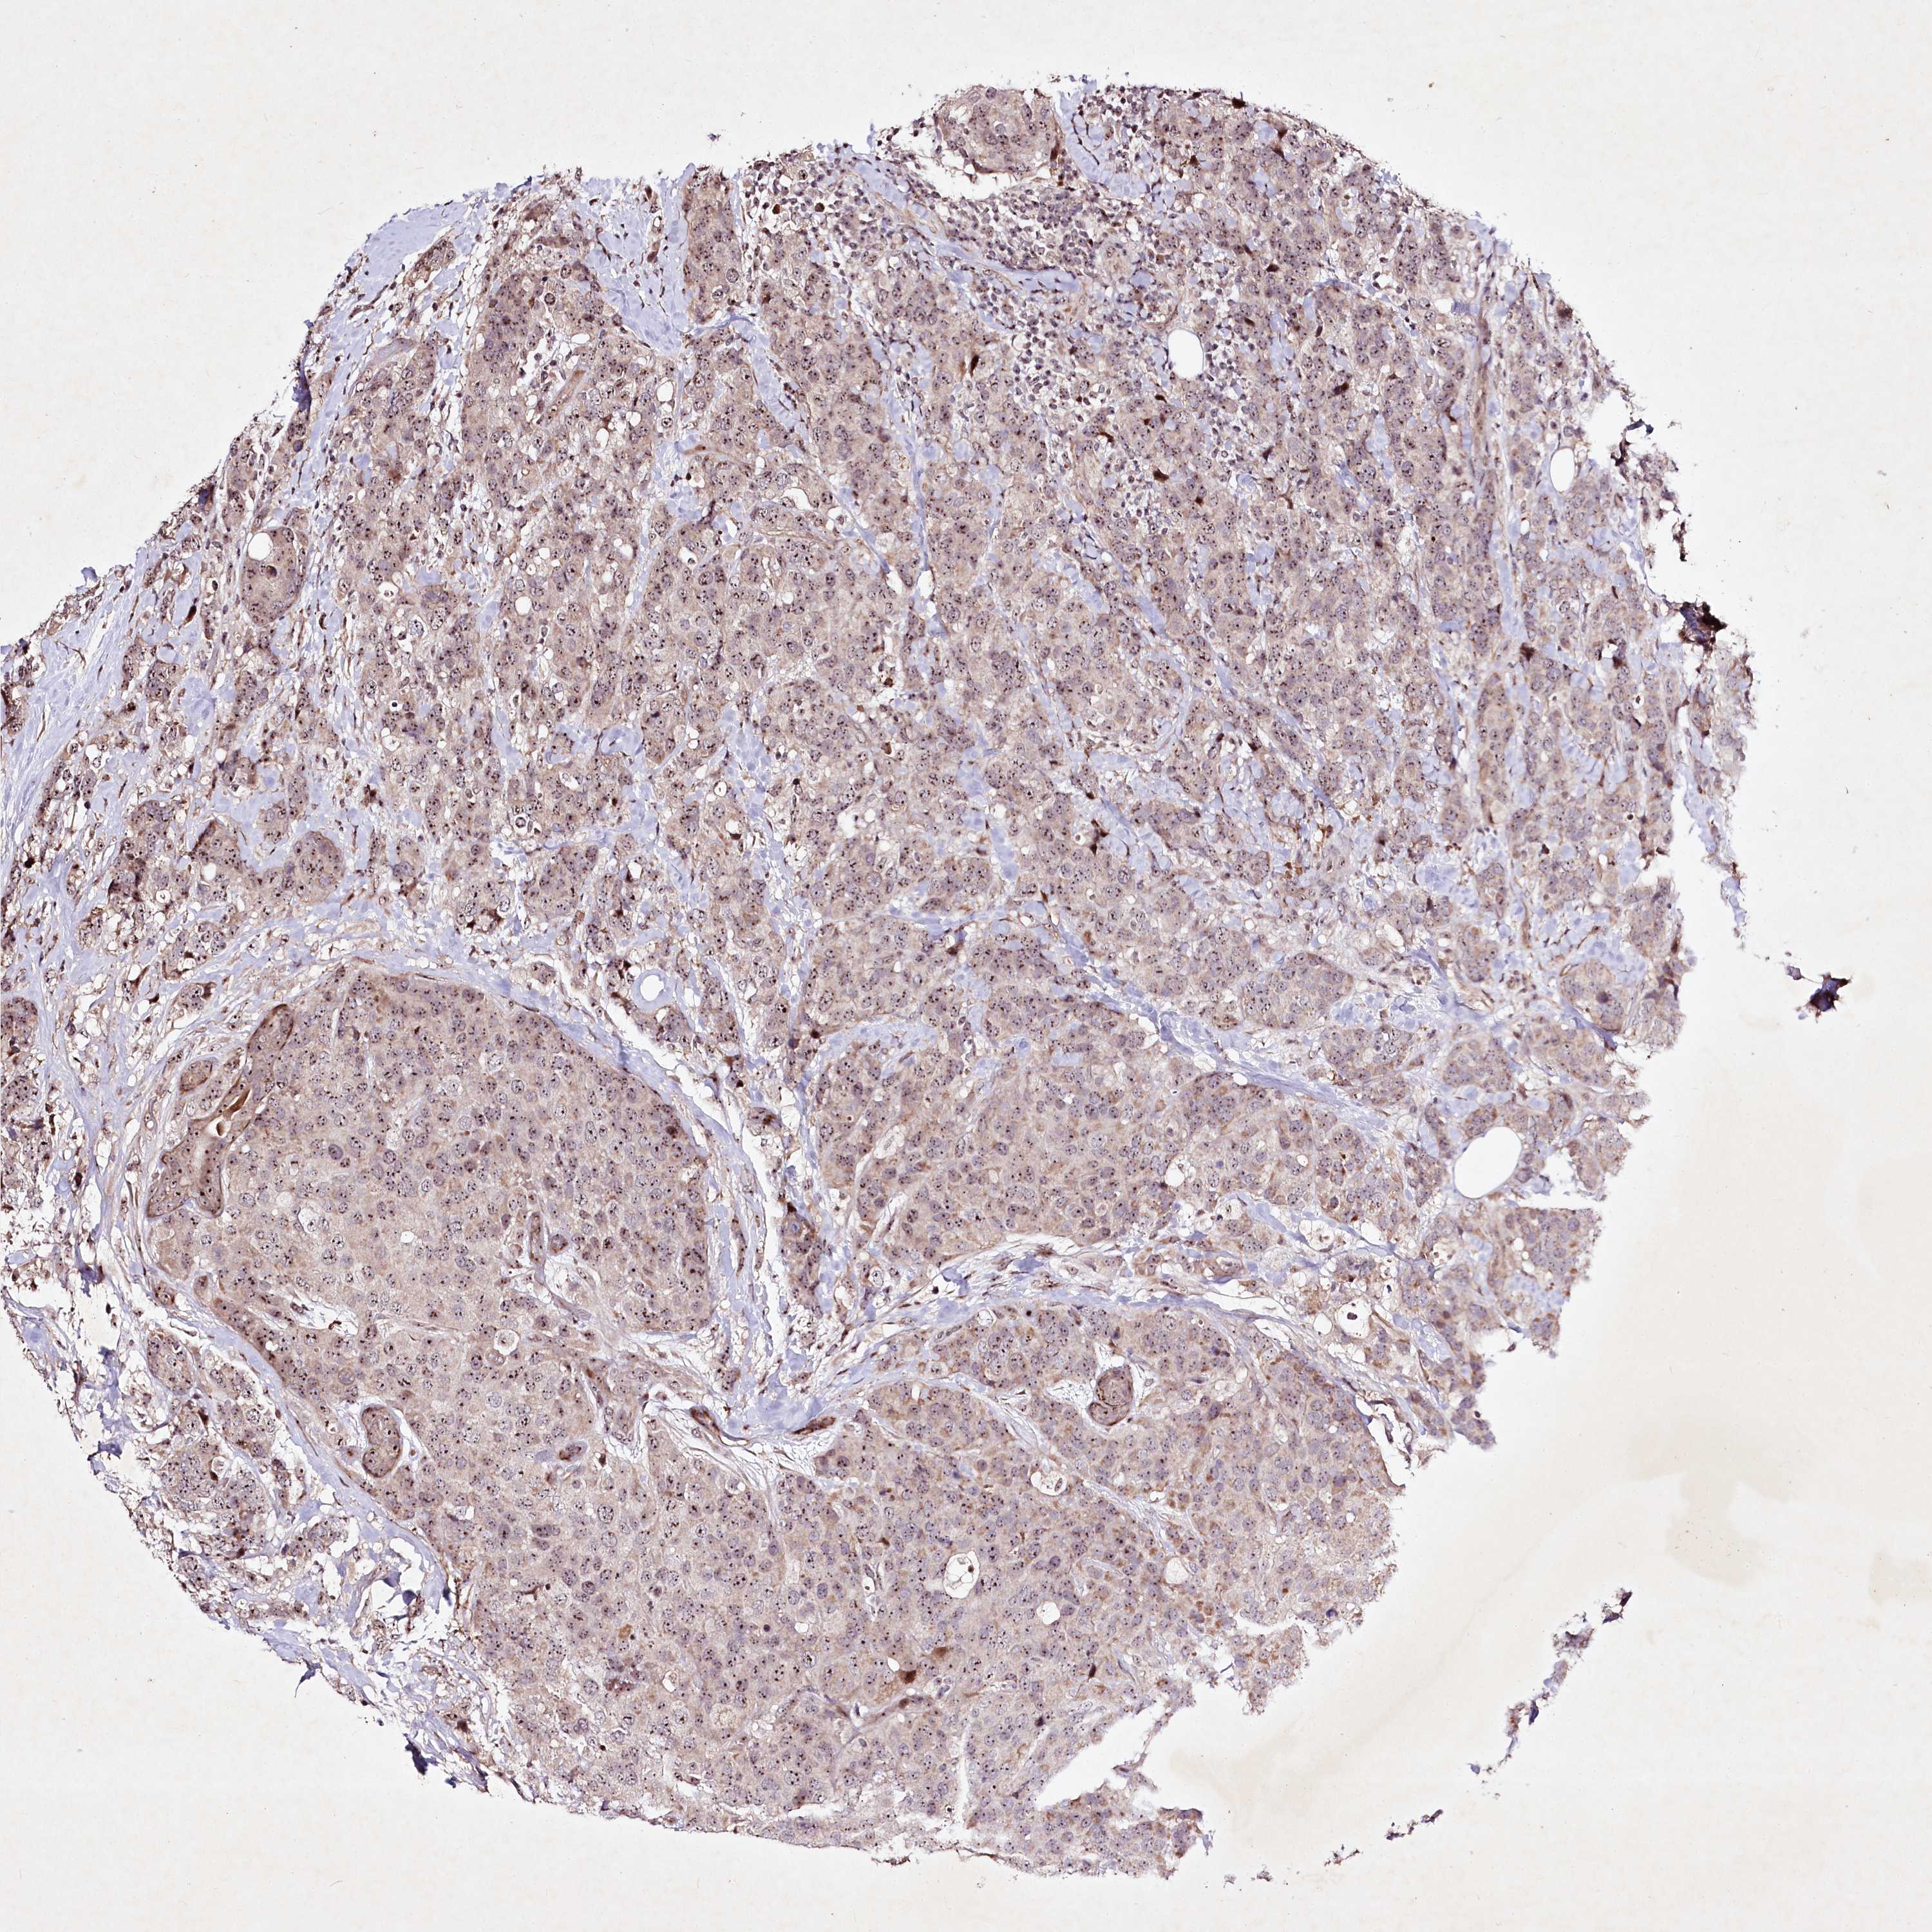

CANCER BREAST CANCER Show tissue menu

BRCA TCGA BRCA VALIDATION PROTEIN EXPRESSION